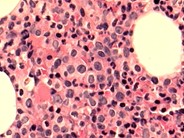

A 64-year-old man presented to our institution with a several-year history of chronic intermittent macrocytic anemia, leukocytosis, and monocytosis. A complete blood count showed a WBC of 13.6 x 109/L (39.6% monocytes), absolute monocyte count of 5.4 x 109/L; hemoglobin 12.3 g/dL; and platelets 141 x 109/L. The peripheral blood smear and bone marrow aspirate smear demonstrated frequent atypical monocytes (panels A-B, Wright-Giemsa stain, 50x magnification) and numerous megakaryocytes with dysplastic features, including small size, hypolobation, and abnormal chromatin pattern (panels C-E, Wright-Giemsa stain, 50x magnification). The core biopsy was hypercellular (80%) and demonstrated dysplastic megakaryocytes (panel F, hematoxylin and eosin, 20x magnification). Concurrent flow cytometry identified an increased monocytic population with partial dim expression of CD56 and 95% classical monocytes lacking CD16 expression (panels G-H). Subsequent myeloid next-generation sequencing (NGS) revealed pathogenic variants in KRAS and U2AF1, supporting the diagnosis of chronic myelomonocytic leukemia, type 1, myeloproliferative subtype (CMML-MP).